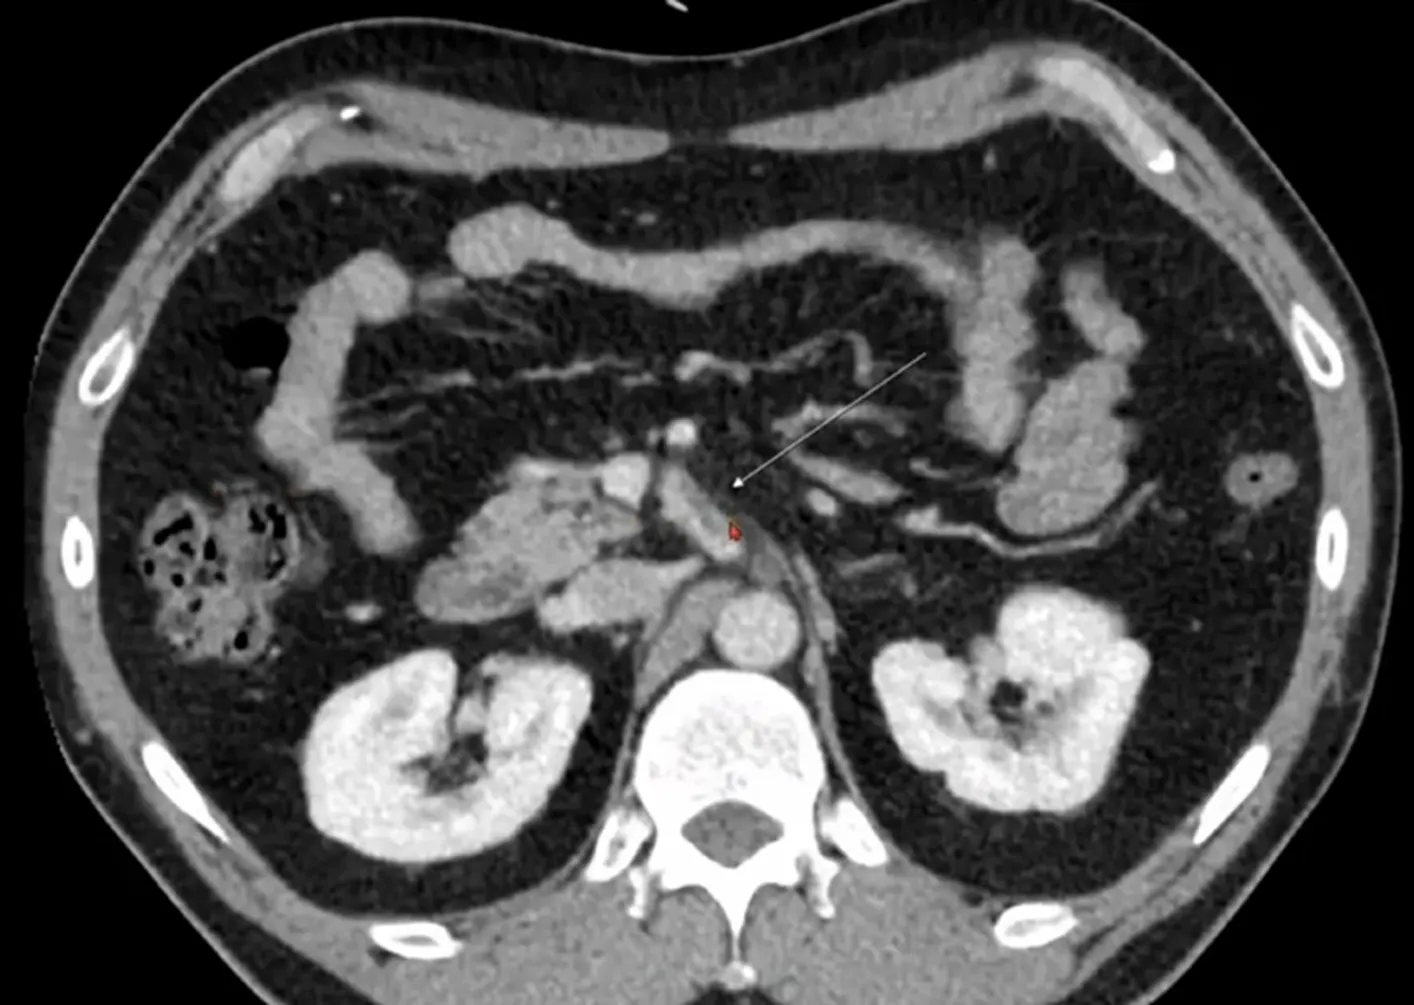

Case 10-1

•

M/94

C/C: abdominal pain

Hx : sigmoid colon cancer s/p anterior resection , AAA s/p EVAR, s/p PTGBD insertion

Lab: CRP 14.9mg/dL, Hb 9.6g/dL

Contained rupture